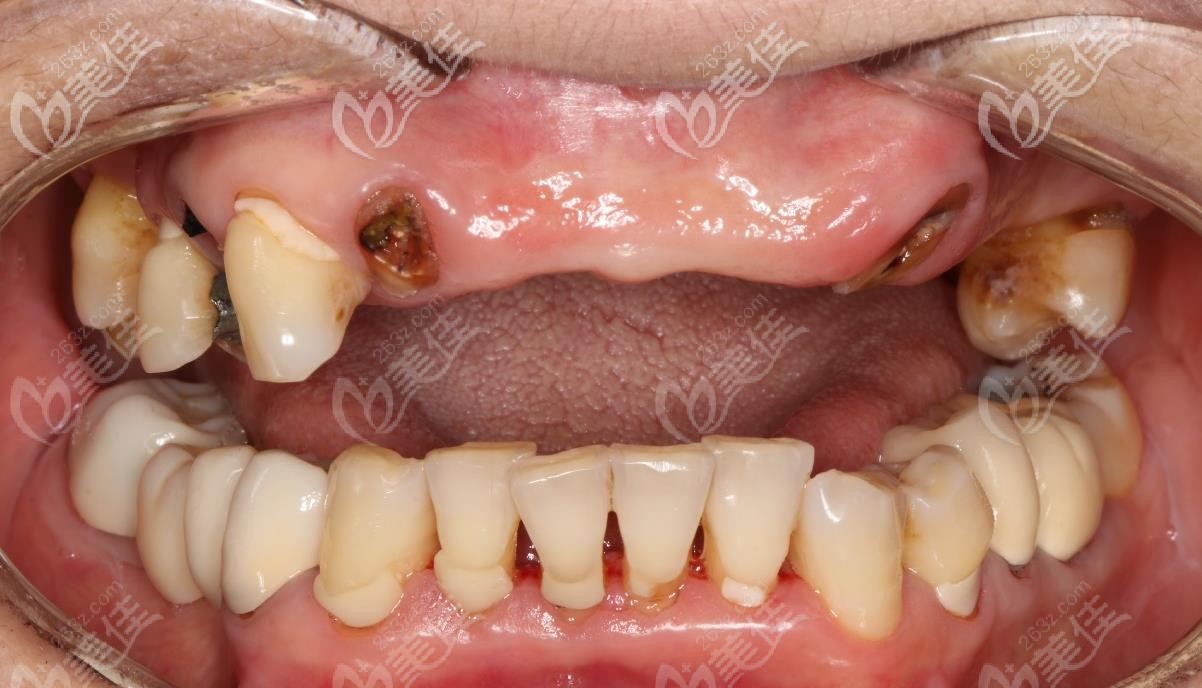

術(shù)前照片:

64歲阿姨口內(nèi)檢查:多顆牙缺失,深覆合深覆蓋,12、14、22殘根,牙體變紅,13、15、17、27 II-III°松動,余牙缺失。

診斷結(jié)果:牙列缺損,牙周炎,牙體缺損